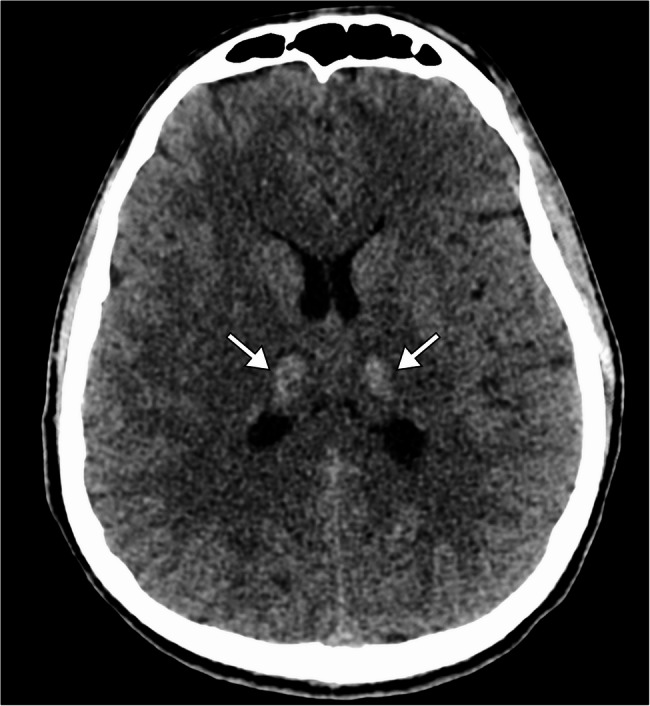

Case presentation: A 19-year-old previously healthy male presented with a two-day history of fever, headache, altered mental status, and seizures. On admission, he was febrile, with impaired consciousness. Initial investigations showed leukocytosis, elevated C-reactive protein, and cerebrospinal fluid analysis indicative of inflammation without bacterial or fungal pathogens. Brain MRI revealed bilateral symmetrical lesions in the thalami, putamen, and brainstem, consistent with acute necrotizing encephalopathy. Polymerase chain reaction testing of cerebrospinal fluid and nasopharyngeal swabs confirmed adenovirus as the causative agent. The patient was managed with seizure control, corticosteroids for cerebral edema, and supportive care, including mechanical ventilation and physiotherapy. Follow-up imaging demonstrated regression of thalamic and pontine lesions. The patient showed partial neurological recovery but required transfer to a long-term care facility for rehabilitation, with persistent functional disability.